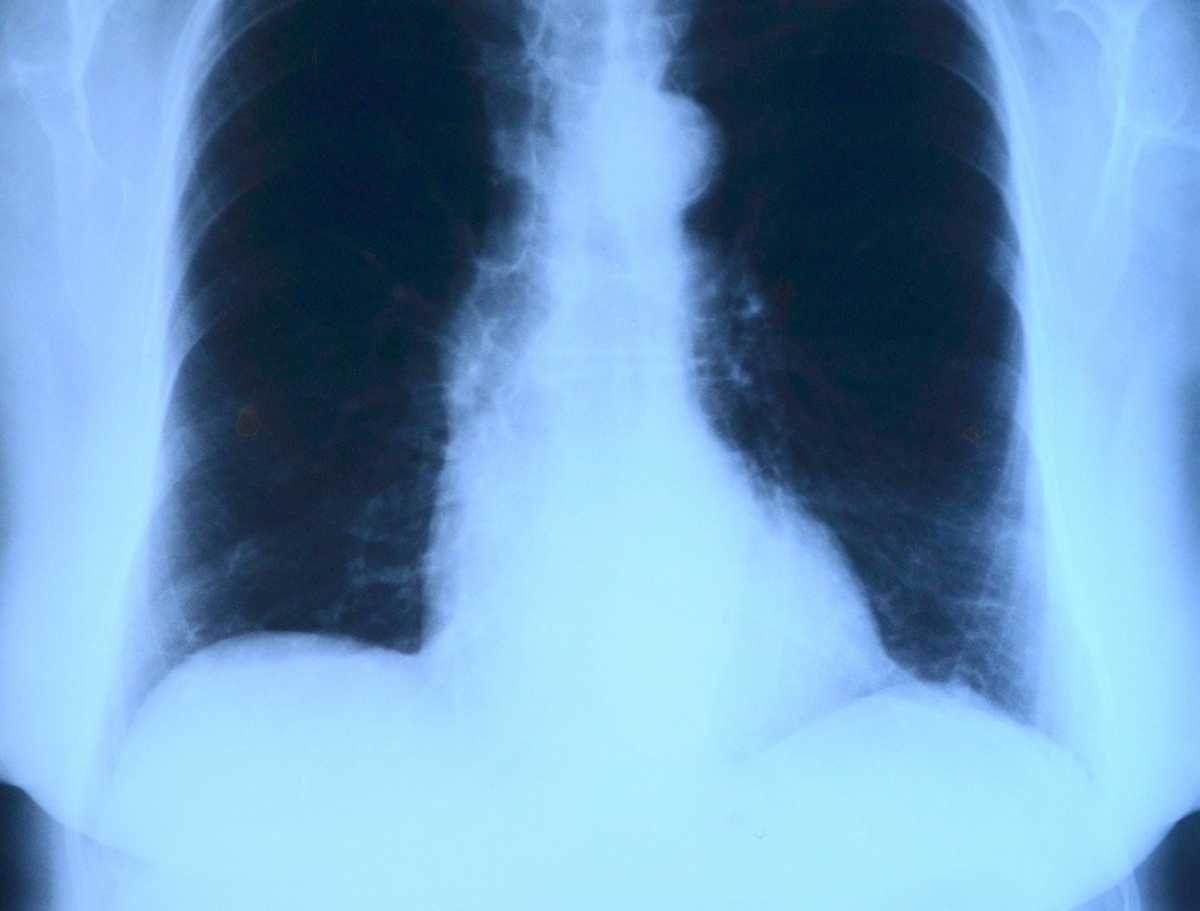

Поражение Легких При Коронавирусе Фото Рентгена

Поражение Легких При Коронавирусе Фото Рентгена 111 фото